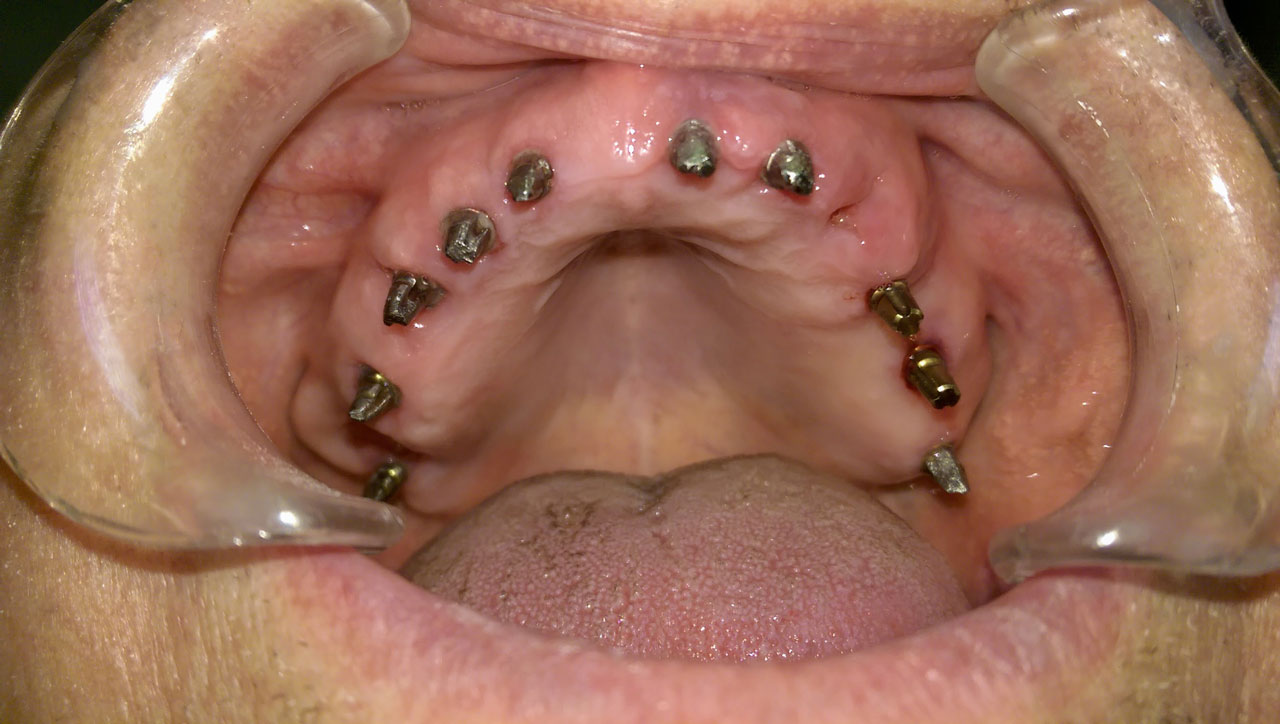

2 nap alatt varázsoltuk ezt a szép esztétikus alsó, felső körhídat implantátumokkal megtámasztva a korábban elhanyagolt szájba. Az 1. nap 26 fogat távolítottunk el, mert annyira rossz állapotban voltak, és rögtön azonnal terhelhető IHDE svájci implantátumokat raktunk be, fentre 8, lentre 6 darabot. A sebeket összevarrtuk és intraorális szkennerrel digitális lenyomatot vettünk. 2 nap múlva pedig beragasztottuk a kész PMMA műanyag körhidakat. Dr. Kelemen Péter és a Symbion Fogtechnika munkája.

Teljes fogatlanság helyreállítása 2 nap alatt azonnal terhelhető svájci IHDE implantátumokkal és PMMA műanyag hidakkal. Intraorális szkennerrel vettünk lenyomatot az implantáció után, és erre a digitális mintára készítette el a fogtechnika a hidak digitális tervezését, majd faragta ki műanyagból. Ezt a gyors munkát az azonnal terhelhető implantátumok és a digitális lenyomat, tervezés segítségével tudtuk megcsinálni mindössze 2 nap alatt. Dr. Kelemen Péter és a Symbion Fogtechnika munkája.